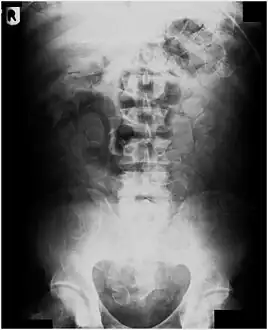

Routine detection of the smuggled packets is extremely difficult, and many cases come to light because a packet has ruptured or because of intestinal obstruction. Unruptured packets may sometimes be detected by rectal or vaginal examination, but the only reliable way is by X-ray of the abdomen. Hashish appears denser than stool, cocaine is approximately the same density as stool, while heroin looks like air.[11][12]

Dx by: Abdominal radiograph, physical evidence of packet, exploratory laparotomy to remove additional packets, sigmoidoscopy.... These were found INSIDE the patient's bowel.... Cocaine packets recovered in the Emergency Department from rectal cavity of patient. Cocaine is stuffed into latex glove fingers and tied. Condoms may also be used - but are more expensive.